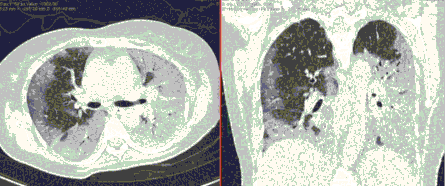

Методы лучевой диагностики применяют для выявления COVID-19 пневмоний, их осложнений, дифференциальной диагностики с другими заболеваниями легких, а также для определения степени выраженности и динамики изменений, оценки эффективности проводимой терапии.

К методам лучевой диагностики патологии ОГК пациентов с предполагаемой/установленной COVID-19 пневмонией относят:

- Обзорную рентгенографию легких (РГ),

- Компьютерную томографию легких (КТ),

- Ультразвуковое исследование легких и плевральных полостей (УЗИ).

Стандартная РГ имеет низкую чувствительность в выявлении начальных изменений в первые дни заболевания и не может применяться для ранней диагностики. Информативность РГ повышается с увеличением длительности течения пневмонии. Рентгенография с использованием передвижных (палатных) аппаратов является основным методом лучевой диагностики патологии ОГК в ОРИТ. Применение передвижного (палатного) аппарата оправдано и для проведения обычных РГ исследований в рентгеновском кабинете. В стационарных условиях относительным преимуществом РГ в сравнении с КТ являются большая пропускная способность. Метод позволяет уверенно выявлять тяжелые формы пневмоний и отек легких различной природы, которые требуют госпитализации, в том числе направления в ОРИТ.

КТ имеет высокую чувствительность в выявлении изменений в легких, характерных для COVID-19. Применение КТ целесообразно для первичной оценки состояния ОГК у пациентов с тяжелыми прогрессирующими формами заболевания, а также для дифференциальной диагностики выявленных изменений и оценки динамики процесса. КТ позволяет выявить характерные изменения в легких у пациентов с COVID-19 еще до появления положительных лабораторных тестов на инфекцию с помощью МАНК. В то же время, КТ выявляет изменения легких у значительного числа пациентов с бессимптомной и легкой формами заболевания, которым не требуется госпитализация. Результаты КТ в этих случаях не влияют на тактику лечения и прогноз заболевания при наличии лабораторного подтверждения COVID-19. Поэтому массовое применение КТ для скрининга асимптомных и легких форм болезни не рекомендуется. При первичном обращении пациента с подозрением на COVID-19 рекомендуется назначать КТ только при наличии клинических и инструментальных признаков дыхательной недостаточности (SpO2 < 95%, ЧДД > 22).

3. Применение лучевых методов у пациентов с симптомами ОРВИ легкой степени тяжести и стабильном состоянии пациента, возможно только по конкретным клиническим показаниям, в том числе при наличии факторов риска, при условии достаточных технических и организационных возможностей. Методом выбора в этом случае является КТ легких по стандартному протоколу без внутривенного контрастирования или РГ при ограниченной доступности КТ. Использование УЗИ в этих случаях нецелесообразно. Применение КТ исследования в сроки ранее 3 - 5 дней с момента появления симптомов заболевания, а также при отсутствии клинических проявлений поражения бронхолегочной системы является нецелесообразным. Выполнение КТ целесообразно при наличии клинических и инструментальных признаков дыхательной недостаточности (SpO2 < 95%, ЧДД > 22), либо при дифференциальной диагностике с другим заболеванием.